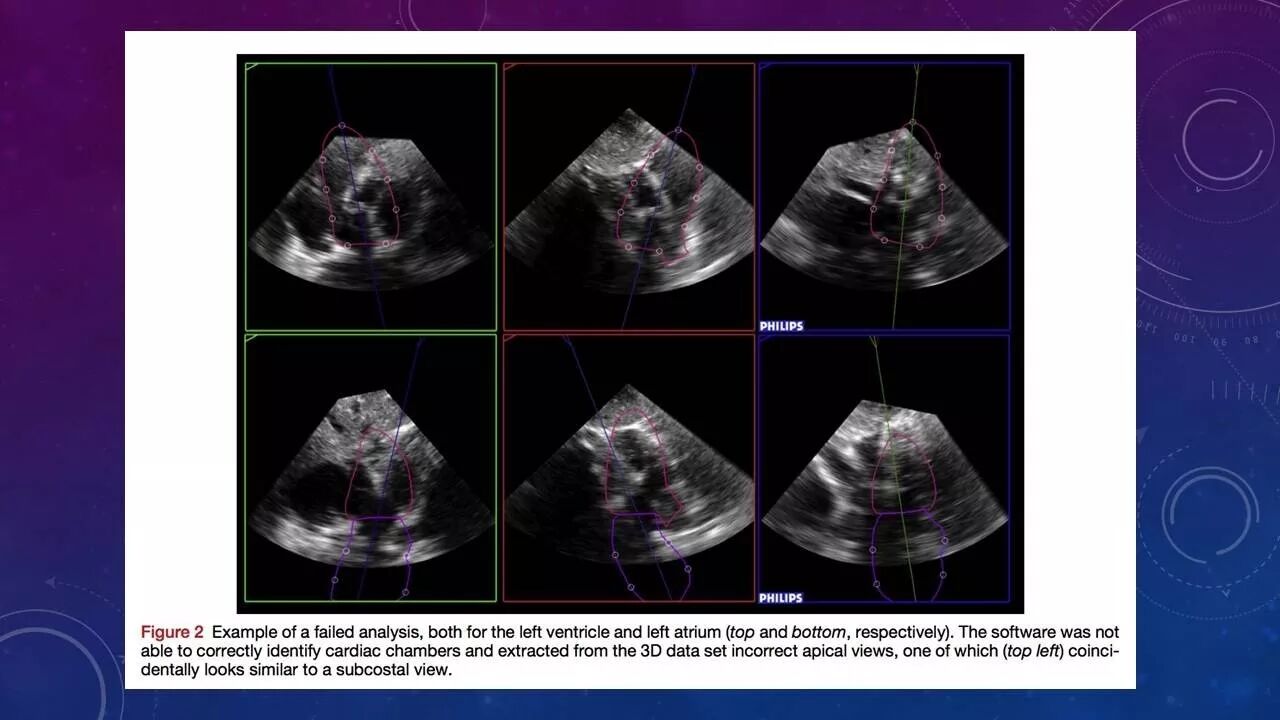

结果:31例(10%)患者未能进行自动分析。图像质量差的患者 (n = 72, 24%)测量结果与参考技术一致性不佳。图像质量良(n = 89, 30%)和好(n = 108, 36%)的患者与对照值相比偏倚小、相关性高。手动编辑后的结果优于未进行校正者。但无经验的检查者进行的调整并不能改善一致性。